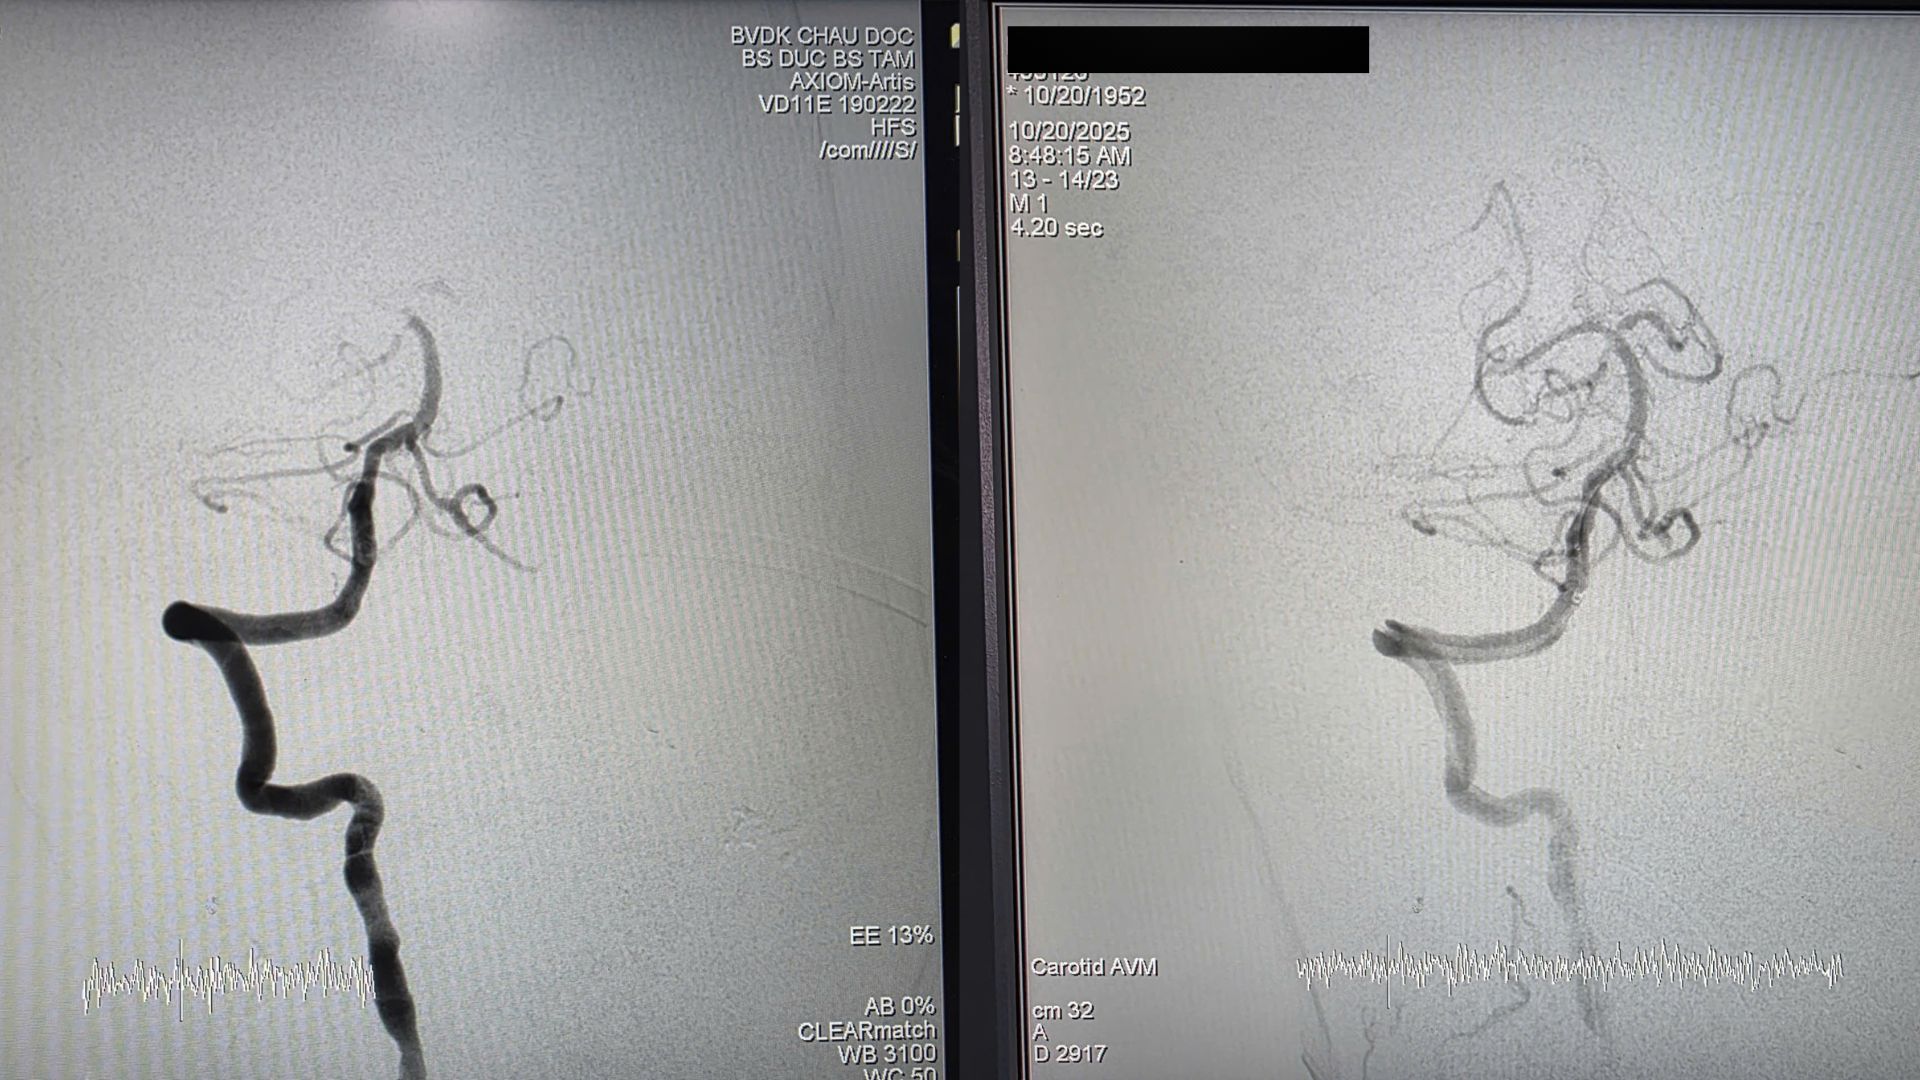

Kết quả chụp cắt lớp vi tính mạch máu (CTA) ghi nhận hình ảnh tắc đỉnh thân nền - vị trí thuộc vùng thân não và tiểu não, được xem là “huyết mạch sống” của hệ thần kinh trung ương. Bệnh nhân được chỉ định can thiệp lấy huyết khối bằng dụng cụ cơ học (EVT) khẩn cấp.

BS.CK2 Hà Minh Đức chia sẻ: "Ở bệnh nhân này có rất nhiều bệnh phối hợp: đột quỵ cấp do tắc động mạch thân nền được tái thông, nhồi máu cơ tim cấp, kèm rung nhĩ cơn. Điều may mắn là bệnh nhân phục hồi tốt sau 24 giờ, hình ảnh CT sau can thiệp gần như không tổn thương nhu mô não".